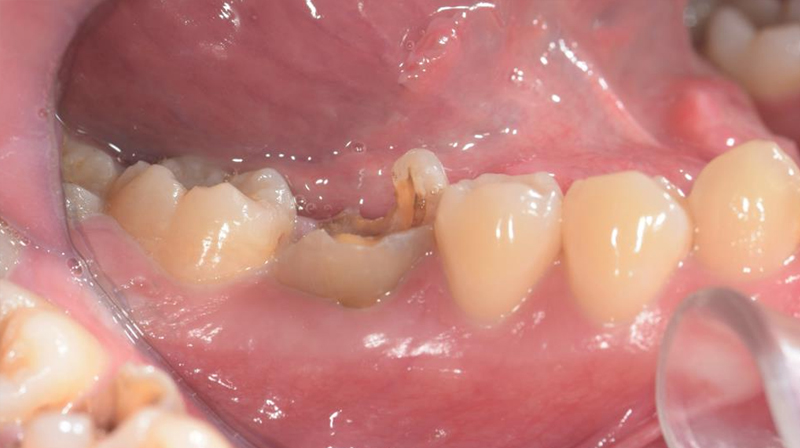

右下第一大臼齒斷裂

拔除右下第一大臼齒

術前